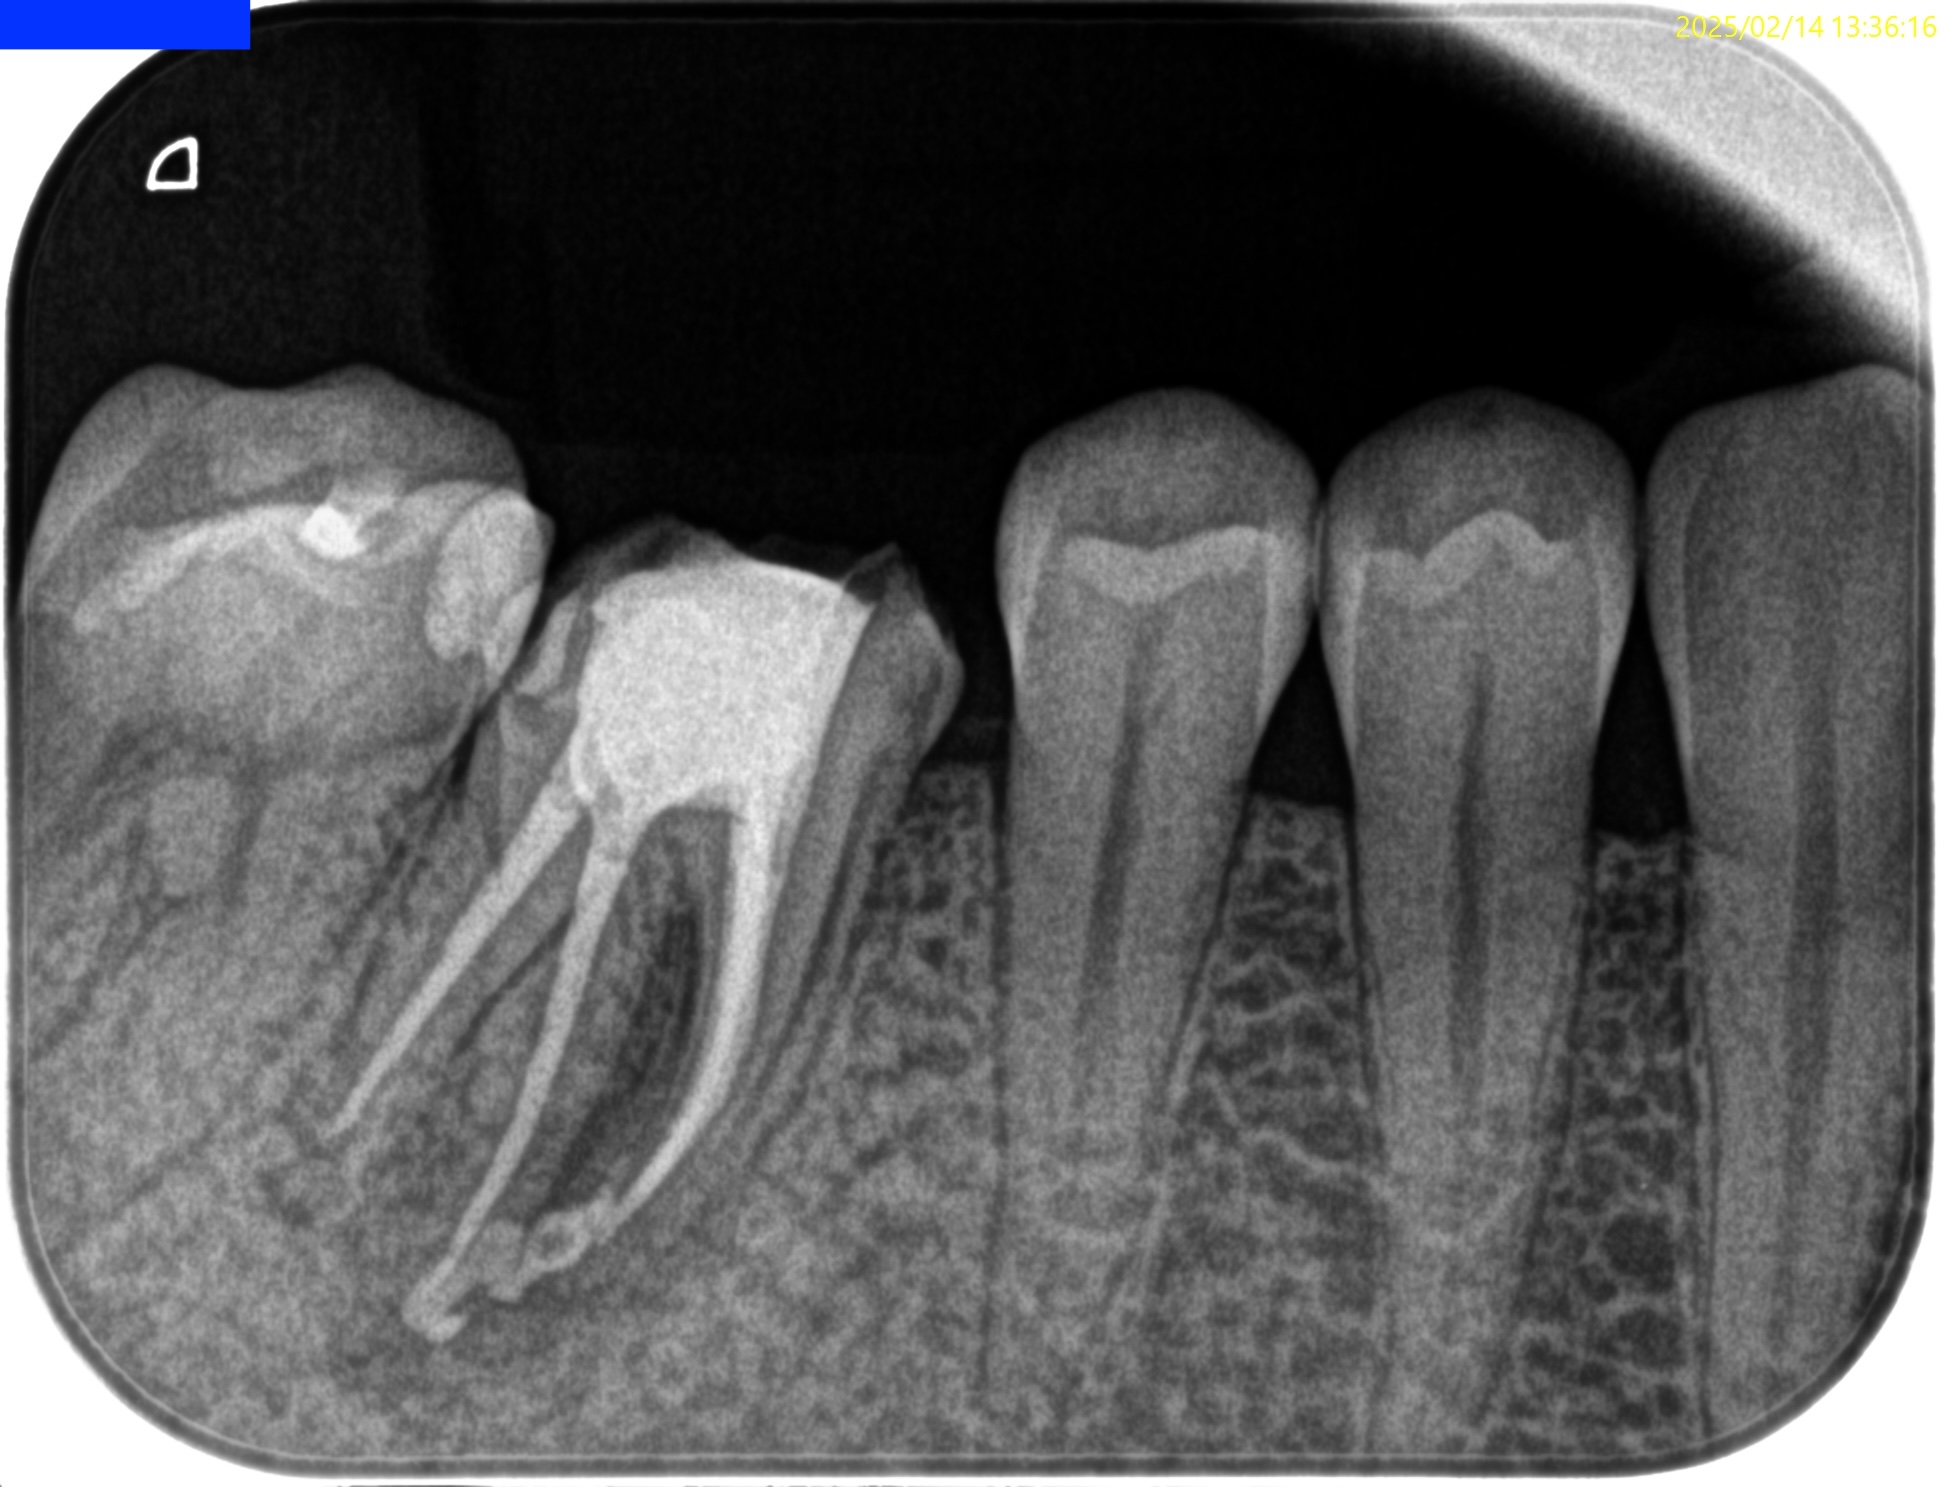

Pre-op Endo test(2025.2.14)

MB

ML

D

Radix

そこそこ湾曲度合いが強いRadix Entomolarisを有する#30だ。

が、D以外の根管はほぼ適切な根管治療がなされていない。

Radixにおいては未着手だ。

Pre-op Endo diagnosis(2025.2.14)

Pulp Dx: Previously treated

Periapical Dx: Symptomatic apical periodontitis

Recommended Tx: Re-RCT